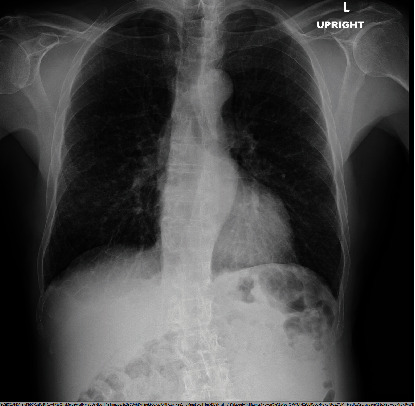

Background: Lymphangitic carcinomatosis (LC), a hallmark of advanced metastatic cancer with a poor prognosis, primarily impacts the lymphatic system of the lungs, manifesting as progressive breathlessness, cough, or hemoptysis. While prostate cancer commonly metastasizes to bones and regional lymph nodes, lung involvement is rare. This case features a patient in generally good health who presented with an insidious dry cough, leading to a diagnosis of Stage 4 prostatic adenocarcinoma with rare lymphangitic spread to the lungs. Case Presentation: A 70-year-old male in good health presented with chest tightness, a dry cough, and sudden left testicular swelling. Imaging revealed interstitial lung markings, severe left hydronephrosis, and prostatomegaly. A prostate biopsy confirmed adenocarcinoma. A PET-CT scan raised significant concern for LC, prompting the initiation of urgent inpatient chemotherapy with docetaxel. Conclusion: LC is a metastatic pattern commonly associated with solid tumors, particularly breast, gastric, and lung cancers. Its occurrence in prostate cancer is exceptionally rare. This condition is typically linked with advanced disease and a poor prognosis, often serving as a critical indicator of an underlying malignancy that may otherwise go undetected.

背景:淋巴管癌肿(LC)是预后不良的晚期转移性癌症的标志,主要影响肺部淋巴系统,表现为进行性呼吸困难、咳嗽或咯血。虽然前列腺癌通常会转移到骨骼和区域淋巴结,但肺部受累的情况并不多见。本病例中的患者总体健康状况良好,但出现隐匿性干咳,最终被诊断为前列腺腺癌 4 期,并伴有罕见的肺部淋巴管转移。病例介绍:一名 70 岁男性,健康状况良好,因胸闷、干咳和突发性左侧睾丸肿胀就诊。影像学检查发现肺间质性病变、严重的左肾积水和前列腺肿大。前列腺活检证实为腺癌。PET-CT 扫描显示该患者患有 LC,这促使他接受了多西他赛住院化疗。结论LC 是实体瘤(尤其是乳腺癌、胃癌和肺癌)常见的转移模式。在前列腺癌中出现这种情况极为罕见。这种情况通常与晚期疾病和不良预后有关,通常是潜在恶性肿瘤的一个重要指标,否则可能无法发现。